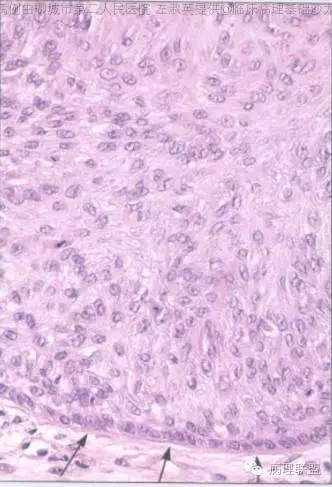

部位表浅,境界较为清楚,伴有不全角化;病变与表皮相连,由浅染细胞构成,周边细胞栅栏状排列;毛囊周边上皮环抱状改变;细胞无异型,核分裂看不太清(就知道这么一丢丢)@左淑英

@刘香丽 后面会有总结的,先看看书,记忆更好,外毛根鞘瘤:低倍看内生性生长,淡染或透明的鳞状细胞构成,边缘栅栏状排列的基地样细胞,外有嗜伊红地基底膜样物质。